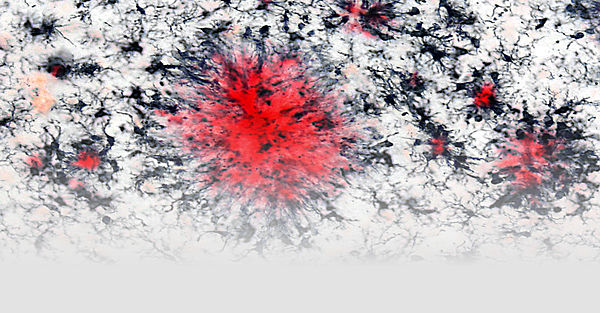

Eine Aktivierung des Immunsystems des Gehirns ist Teil fast aller neurologischer Erkrankungen und das Auftreten der Alzheimer-Demenz (AD) wurde kürzlich mit genetischen und epigenetischen Veränderungen von immun-relevanten Genen in Verbindung gebracht. Dies deutet auf eine signifikante Beteiligung des Immunsystems an der Alzheimer-Demenz hin. Die Immunantwort, die als Teil der Alzheimer-Erkrankung auftritt, wird hauptsächlich durch die Hirn-ansässigen Makrophagen, sogenannten Mikroglia, vermittelt, und diese Zellen sammeln sich besonders um die unlöslichen Ablagerungen an, die als Teil der Erkrankung im Gehirn auftreten. Jedoch sind verschiedene Aspekte der Rolle von Mikroglia in der Alzheimer-Pathogenese weiterhin ungeklärt. Weiterhin ist unklar, wie Entzündungsprozesse außerhalb des zentralen Nervensystems die Immunantwort des Gehirns beeinflussen können.

Zu diesem Zweck verwenden wir verschiedene Modelle der peripheren Entzündung und profilieren die Immunantwort der Mikroglia auf sekundäre Reize, einschließlich pathologischer Veränderungen in neurodegenerativen Krankheitsmodellen. Wir isolieren Mikroglia aus dem adulten und gealterten Gehirn und untersuchen deren molekulare Profile (transkriptional, epigenetisch) und Funktionen (phagozytisches Verhalten und Freisetzung entzündlicher Mediatoren). Zusammen mit der Unit Molekulare Bildgebung verwenden wir Multiphotonen-Mikroskopie, um mikrogliales Verhalten im lebenden Gehirn unter entzündlichen Bedingungen zu untersuchen.

In unserer Arbeitsgruppe haben wir vor kurzem gezeigt, dass Mikroglia in der Lage sind, sich an vorherige Entzündungsprozesse zu "erinnern" und ihre Immunreaktion an nachfolgende Reize anzupassen. Besonders bemerkenswert ist, dass diese langfristigen Anpassungen der mikroglialen Immunreaktion signifikante Auswirkungen auf die Hirnpathologie in Mausmodellen hatten. Darüber hinaus konnten wir zeigen, dass diese adaptive Reaktion auf der epigenetischen Umprogrammierung von Mikrogliazellen basiert und unsere Ergebnisse geben Aufschluss darüber, wie Mikroglia verschiedene entzündliche Reize über lange Zeiträume integrieren können (Wendeln et al., Nature 2018). Dies war die erste Beschreibung des "angeborenen Immungedächtnisses" im Gehirn, und ein solches Gedächtnis der Immunzellen im Gehirn könnte möglicherweise erklären, wie entzündliche Zustände bei menschlichen Patienten (wie Infektionen, aber auch Diabetes oder Adipositas) das Risiko für die Entstehung der Alzheimer-Erkrankung erhöhen oder das Fortschreiten der neurodegenerativen Krankheitspathologie verändern können (Neher und Cunningham, Trends in Immunology, 2019).